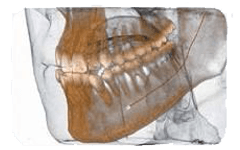

Radiografia specifica per la bocca

Lo studio si avvale di specifiche strumentazioni per assicurarti un’accurata analisi ortodontica. In primis, lo staff medico si affida all’alta tecnologia del sistema Cone Beam NewTon 5G XLUno, fondamentale per settori medici quali implantologia, endodonzia, chirurgia orale e ortodonzia, in grado di creare immagini 3D capaci di mostrare patologie potenziali e anomalie strutturali con una precisione senza precedenti; dall’altra si sottolinea la presenza della tecnologia SafeBeam™, il sistema più sicuro sia per i pazienti che per lo staff medico. Grazie a questo strumento, gli esperti eliminano qualsiasi possibilità di esposizioni radioattive, mantenendo un contrasto dell’immagine nitido e definito, a prescindere dalle dimensioni anatomiche o dalla densità ossea osservata.